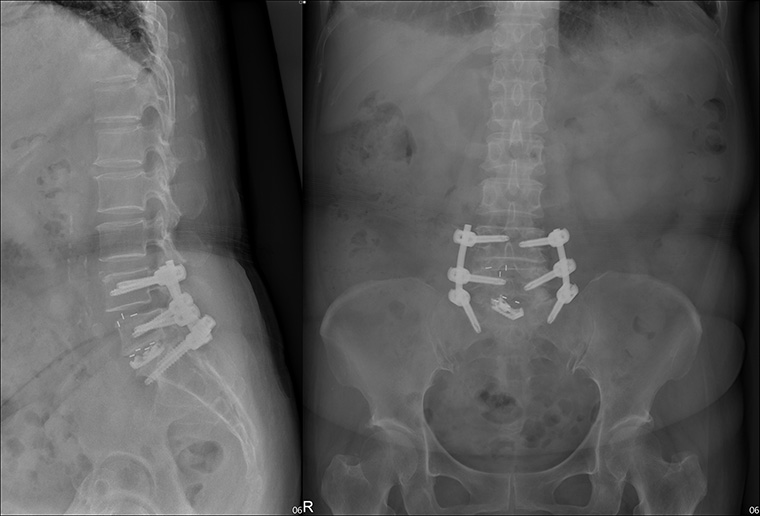

▲醫師採用微創椎間融合術為患者治療,手術傷口小、恢復快。(圖/羅東博愛醫院提供)

羅揚嵐此次以微創椎間融合術為患者治療,切除部分椎間盤、進行部分椎板減壓手術、置入骨釘穩定脊椎,透過精密的顯微影像儀器,手術傷口小、恢復快,術後隔天邱女士就可在病房內接受物理治療師的指導,進行簡單復健並下床活動。未來3個月邱女士只須穿著背架,就可以繼續跟朋友遊山玩水。